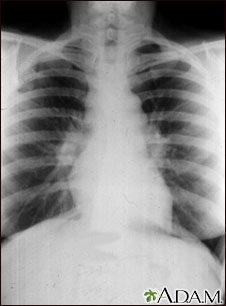

Sarcoid is primarily a lung (pulmonary) disease. In the early stages, a chest film may show enlargement of lymph nodes in the center of the chest near the heart (mediastinum).